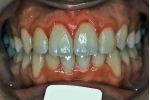

初診時